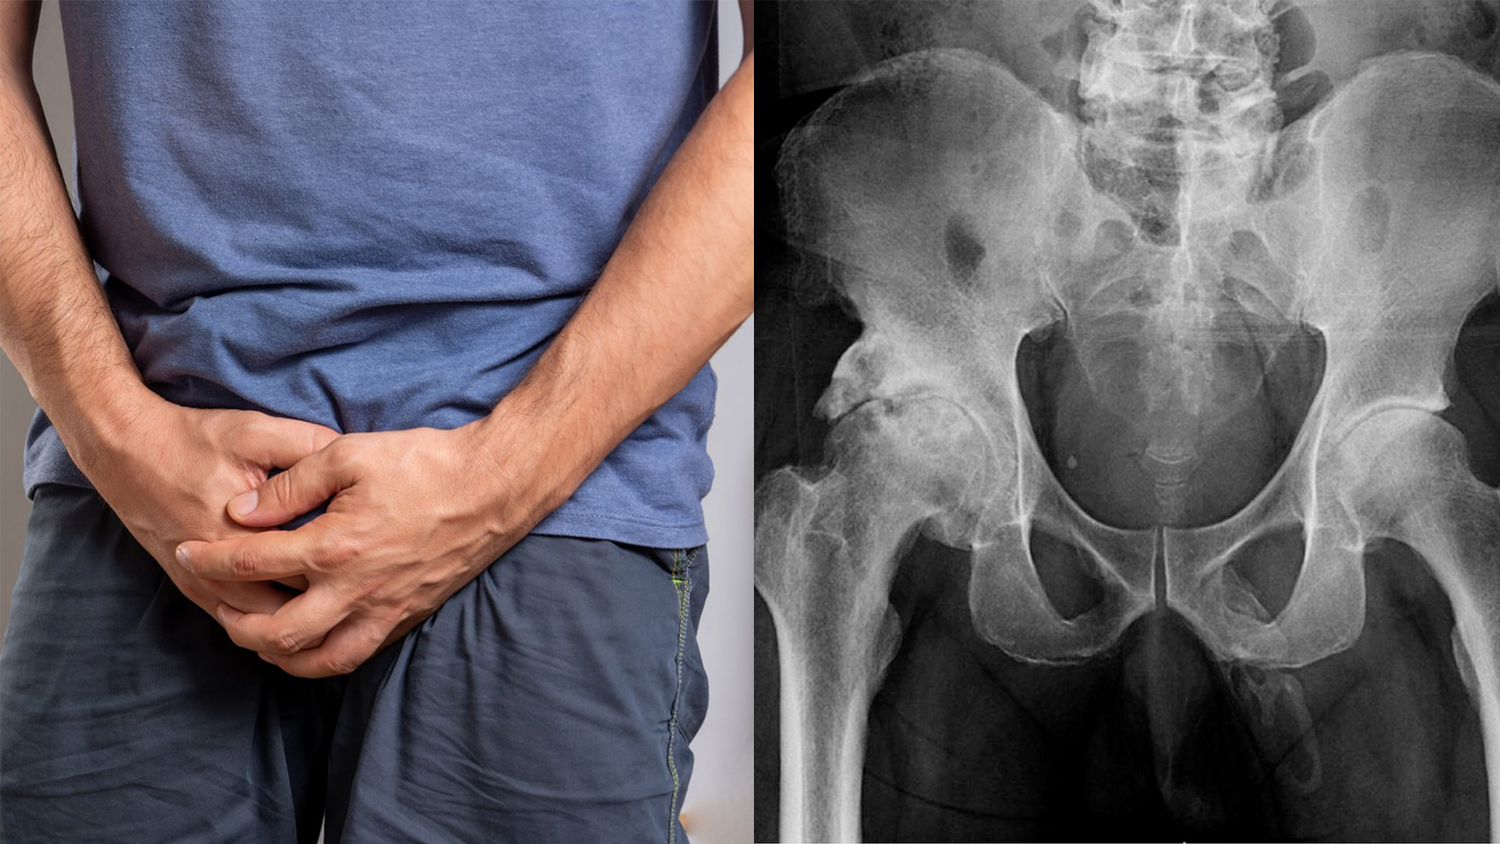

Weil er betrunken gestürzt war, kam ein Mann in die Notaufnahme des Lincoln Medical and Mental Health Center in New York (USA). Soweit unspektakulär. Der 63-Jährige hatte sich wegen Knieschmerzen in Behandlung begeben, klagte aber bei der Untersuchung auch über Schmerzen in seinem Penis.

Die Ärzte fanden aber weder eine Prostata-Schwellung noch einen ungewöhnlichen Ausfluss, das die Penisschmerzen erklären konnte. Sie führten Röntgenaufnahmen des Beckens durch, um nach Brüchen zu suchen – und entdeckten dabei knochenähnliche Wucherungen in seinem Penis.

Es stellte sich heraus, dass eine seltene Erkrankung namens "Penisverknöcherung" die Ursache war. Sie wird durch die Ablagerung von Kalzium im Weichteilgewebe des Penis verursacht, was zur Bildung einer knöchernen, außerskelettalen Struktur im Inneren des Glieds führt. In der wissenschaftlichen Literatur sind weniger als 40 Fälle von Penisverknöcherung dokumentiert. Wenn sie auftritt, wird sie oft mit der Peyronie-Krankheit in Verbindung gebracht – einer Erkrankung, bei der sich verhärtetes Gewebe am Penis bildet, das ihn krümmt und manchmal zu Erektionsstörungen führt. "Es zeigte sich eine ausgedehnte, plaqueartige Verkalkung entlang der erwarteten Verteilung des Penis", schrieben die Mediziner in ihrem Bericht.

"Typischerweise sind Männer über 40 betroffen, aber auch jüngere Männer können erkranken. Das Ungewöhnliche am Fall des 63-jährigen Patienten war das Vorhandensein einer Verknöcherung im gesamten Penisschaft. Diese findet normalerweise in der Mitte des Penisschaftes statt, aber nur in wenigen Fällen ist der gesamte Schaft betroffen", heißt es im Bericht weiter.